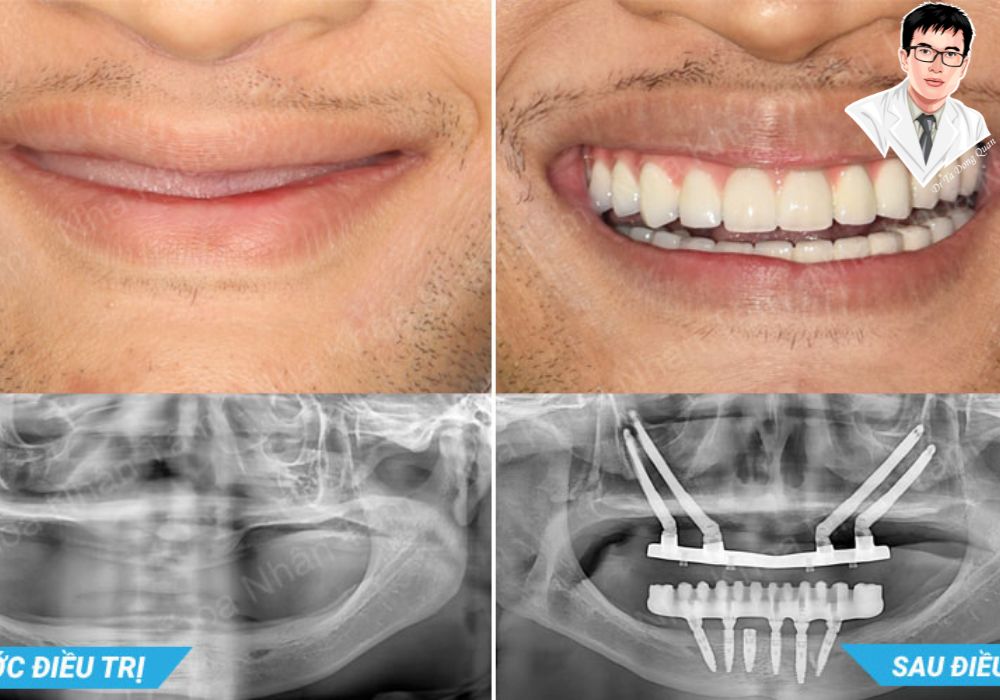

X-quang implant Zygoma hai bên – phù hợp với bệnh nhân tiêu xương hàm nặng.

Từ không răng đến nụ cười hoàn hảo chỉ sau vài giờ!